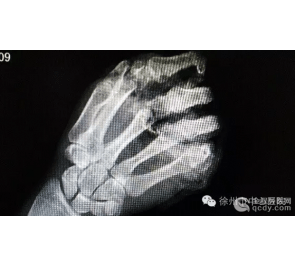

大拇脚趾外翻畸形是常见病,轻者外观不佳,重者疼痛不适,影响行走功能,严重影响人们的生活质量。王爱国提示说,由于国内足外科医生较稀缺,而医疗市场化存在诊疗误导,使拇趾外翻畸形的治疗缺乏科学性,存在较多的误区。

举例来说,对于大拇脚趾外翻畸形,微创手术是最佳选择吗?王爱国认为,微创治疗需要用内窥镜和相关的精密仪器,必须由丰富手术经验的医务人员操作,否则会加重损伤。所谓微创实际只是皮肤切口小而已,手术部位内部创伤更大,因为在镜下操作无法和直视下操作的精确度相比。另外,大拇脚趾外翻畸形是非常复杂的疾病,手术方法上百种,如果是简单的疾病,怎么会出现如此多的手术方法。微创手术操作不当会损伤正常组织,更重要的是,微创手术无法完成复杂操作,如截骨手术,肌腱转位和功能重建等。

“总而言之,微创可以用于简单的骨赘切除和拇收肌切断等手术,对于复杂的拇趾畸形而言,微创手术存在风险,不能达到彻底解决问题的能力,存在商业炒作嫌疑。”